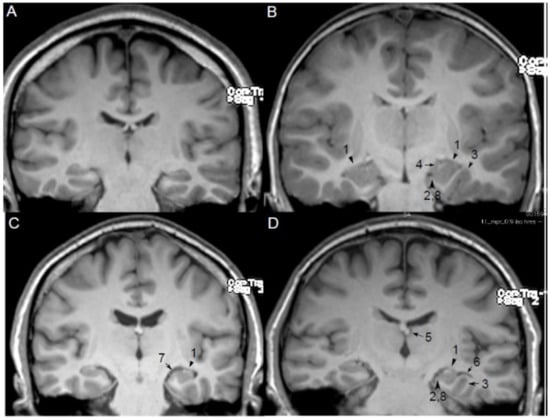

5. MRI Features and Qualitative Diagnosis of HIMAL

- Round or pyramidal shape instead of ovoid shape;

- Medial position of the hippocampus on the hippocampal sulcus;

- The collateral sulcus is excessively deep or “verticalized”;

- Fimbria located medial to the hippocampus;

- Small or displaced fornix;

- Enlarged temporal horn and empty choroid fissure;

- Thickened subiculum;

- Reduced upper horizontal portion of the parahippocampal gyrus.